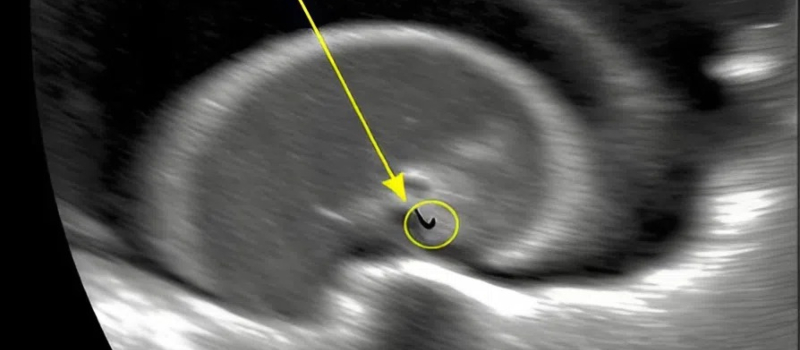

I blinked. Surgery? For stomach pain? My mind spun. Seeing my panic, he explained carefully. The scan revealed something small and dangerous inside her stomach. Something that shouldn’t be there. A pin.

I couldn’t process it. My daughter, my little girl, had swallowed a pin. My thoughts scattered. How? When? I replayed the day in my mind. She had been playing on the floor, surrounded by scattered buttons and threads. One careless moment—one blink—could have caused disaster.